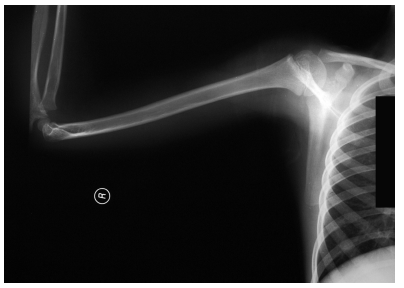

| Figure 1a: standard x-ray carried-out in the emergency room |

| Figure 1b:standard x-ray carried-out in the emergency room |

Male, 7 years and 9 months old; fell from the dad’s motorbike hitting on the floor the right shoulder. Reached the emergency room immediately after the trauma. At the clinical examination presented swelling and deep pain at the pressure on the coracoid and all over the shoulder; the motility was good but it reawaken/stirred pain in particular in abduction. The standard x-ray carried-out in the emergency room suspecting a fracture of the clavicle or humerus (figureure 1 a-b) underlined a light discontinuity at the base of the right coracoid, centering of the humeral head and continuity of the acromio-clavicular joint. Are requested the specific and comparative projections of the left shoulder (figureure 2 a-b) that highlights the separation of the coracoid base with small compound fracture. Is decided for a conservative treatment by applying Desault bandage for 25 days. At the removal, the clinic examination shows light pain at the mobilization of the shoulder and at the pressure on the coracoid. The radiographic exam points out good consolidation of the fracture and his realignment (figureure 3 a-b). At the clinic follow-up after 20 days after the removal of the bandage, the patient does not complain any pain and presents a complete motility of the shoulder.